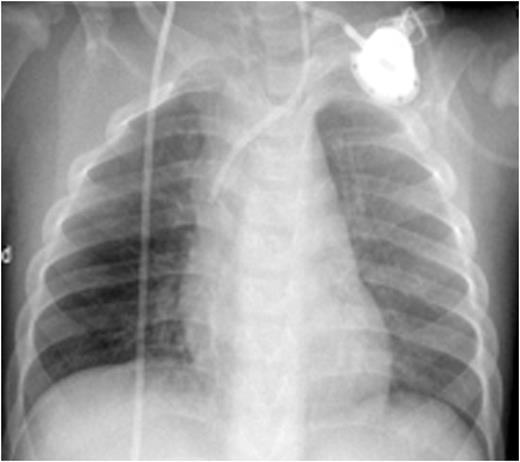

Progressive dissolution of the membranes and exophytic lesions with some blood spotting, was noted, and was associated with decreased oxygen requirements. Improvement in the ligneous eye lesions was also observed. After 4 days he was extubated., but required reintubation after 36 hours due to exhaustion; he was finally extubated 1 week after receiving the first dose of plasminogen. Plasminogen replacement has continued with a regimen of 6.5 mg/kg every second day. There has been progressive dissolution of the membranes with greatly reduced lesions seen after 6 weeks of treatment.

CXR before administration of plasminogen showed atelectasis of the left lung and of the right lower lobe (left panel). Six weeks after initiation of regulalar plasminogen substitution ventilation in both lungs had improved significantly (right panel)